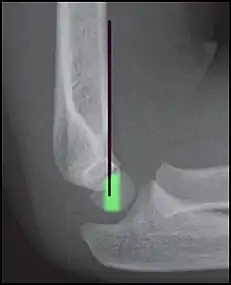

Supracondylar humerus fracture

An elbow X-ray showing a displaced supracondylar fracture in a young child

Percutaneous pinning

Percutaneous pinning are usually inserted over the medial or lateral sides of the elbow under X-ray image intensifier guidance. There is 1.8 times higher risk of getting nerve injury when inserting both medial and lateral pins compared to lateral pin insertion alone. However, medial and lateral pins insertions are able to stabilise the fractures more properly than lateral pins alone. Therefore, medial and lateral pins insertion should be done with care to prevent nerve injuries around elbow region.[3]